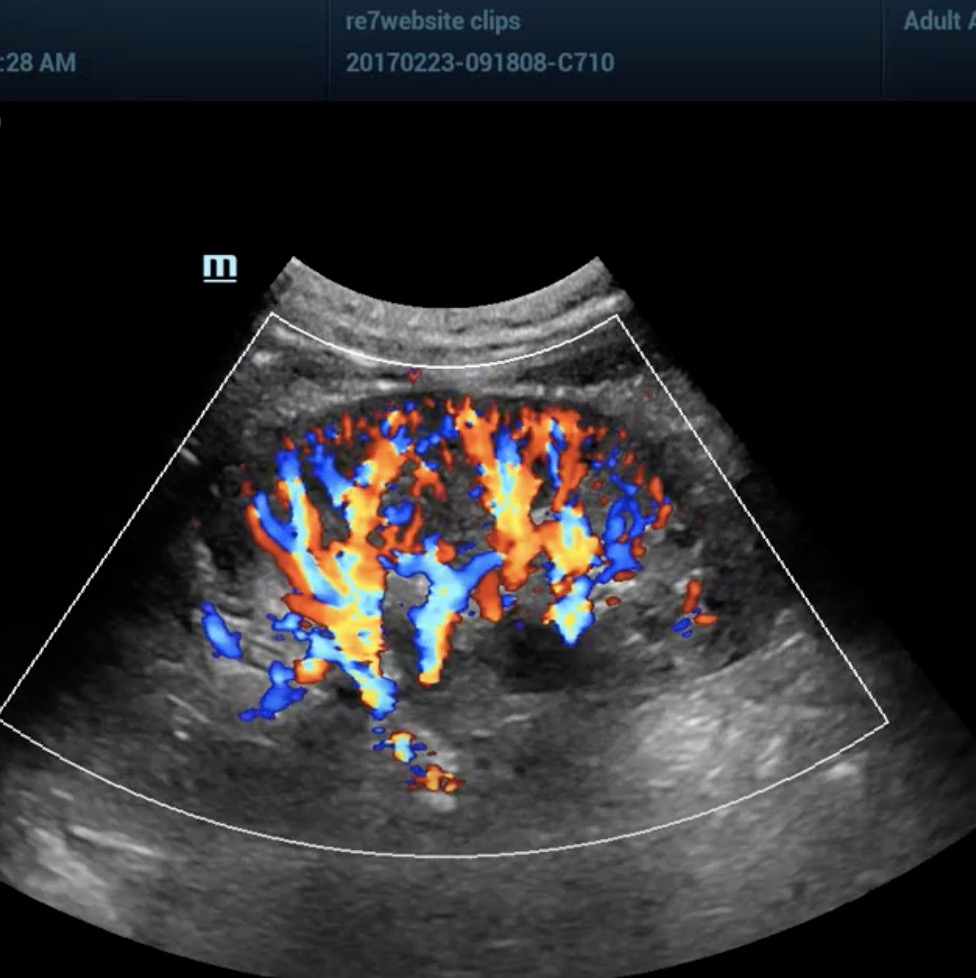

Another unique and patented engineering breakthrough that differentiates ZST from traditional hardware-based beamforming platforms is automated digital Sound Speed Compensation (SSC). Historically, ultrasound imaging systems have been calibrated to the inaccurate assumption that ultrasound propagates through all human soft tissue at a velocity of 1,540 meters per second. In fact, many factors affect the actual speed of sound in a particular tissue and failure to compensate for these differences diminishes and limits spatial and contrast resolution in conventional ultrasound systems. At the touch of a button, SSC automatically samples the tissue being examined and recalibrates the software to reflect its specific speed of sound. The resulting enhancements in image quality provide another powerful clinical tool that increases diagnostic confidence, especially when examining diseased organs and structures at deeper depths.